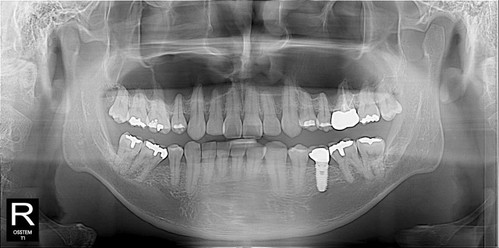

역시 신경손상가능성을 최소화한 후

깔끔하게 발치완료~